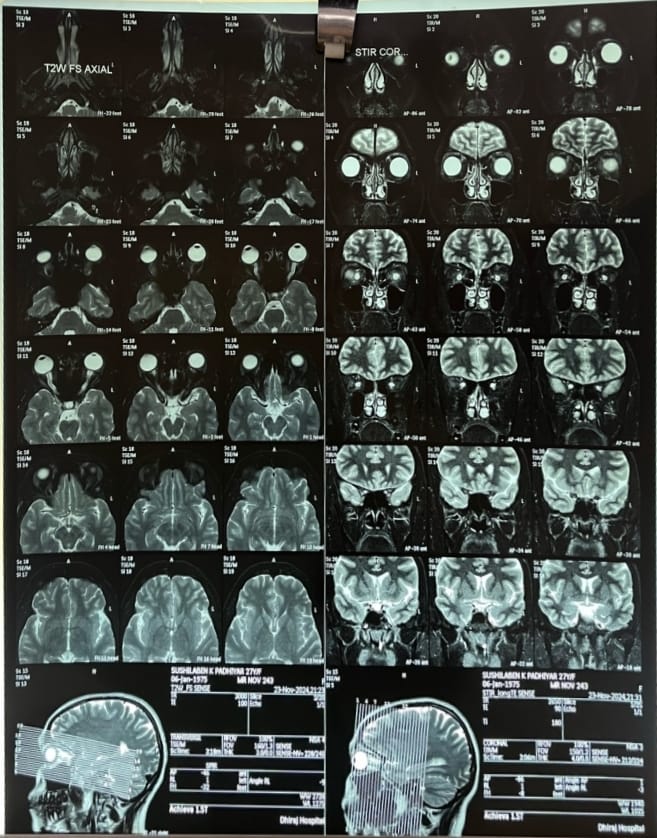

Lumbar puncture was performed at an high opening pressure. Examination of cerebrospinal fluid (CSF) indicated normal cell count, glucose, and protein levels. A bilateral papillary edema could be caused by structural cerebral abnormalities, such as benign or malignant brain tumors, vascular lesions, or inflammation/infections (cerebral abscess), which were ruled out by neurologic and MRI examinations. All inflammatory tests were negative, excluding the possibility of an autoimmune disorder. Chronic intracranial hypertension can be caused by a variety of factors, including tetracycline, blood clots in the brain, high vitamin A intake, and brain tumors. It can also occur without a clear cause based on the patient's medical history. In our case, MRI brain with orbit showed flattening of posterior sclera and protrusion of optic nerve heads along with vertical tortuosity of optic nerve sheath, which was suggestive of possibility of pseudotumor cerebri (fig. 1).

Fig. 1: Mri orbit